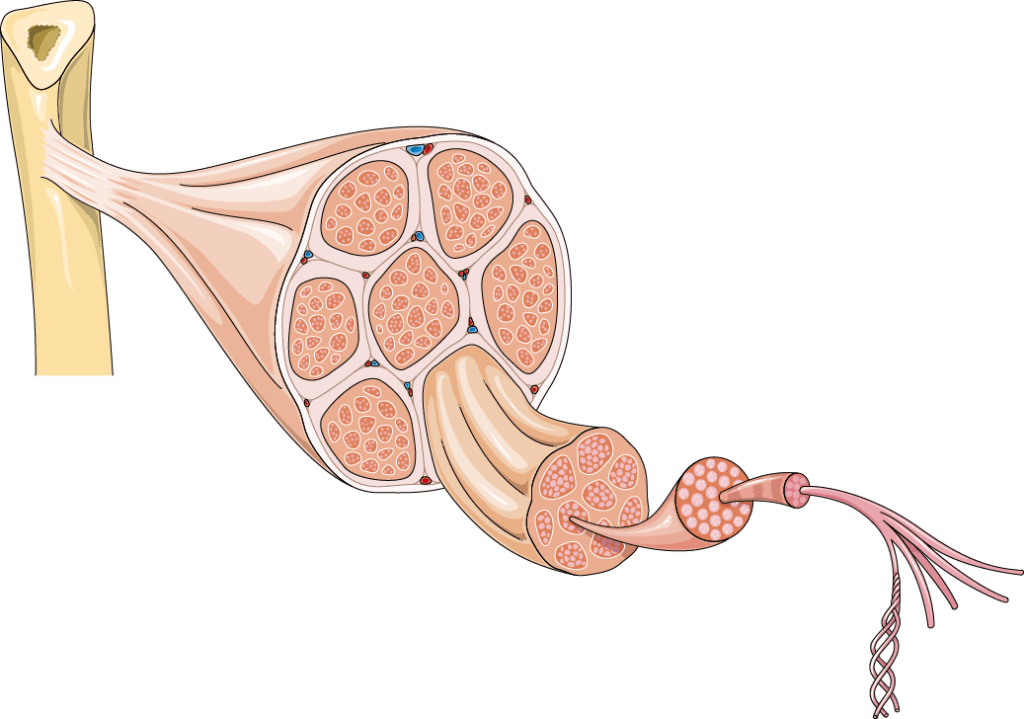

- Tener un conocimiento y una comprensión profundos de la biología, la anatomía y la fisiología, así como de la industria científica y tecnológica.

En la ilustración médica, lo primero que podemos notar es que los dibujos nos ayudan a capturar con precisión ciertas partes u órganos en los que queremos enfatizar, pudiendo incluso aumentar el nivel de detalle para visualizarlos cuanto queramos además de poder ubicarlos en diferentes perspectivas dentro del espacio que ocupan originalmente en nuestro cuerpo, ya sea en 2D o 3D, sin todas las complicaciones que esto significaría al tomar una fotografía.

Sobra decir que las animaciones logradas tanto en dos dimensiones como en tres cada vez son mejores e incluso están trabajando en conjunto con los últimos avances tecnológicos en software y en materia de medicina para mejorar el estudio de padecimientos, enfermedades o son utilizadas en el mismo entrenamiento virtual para cirugías.